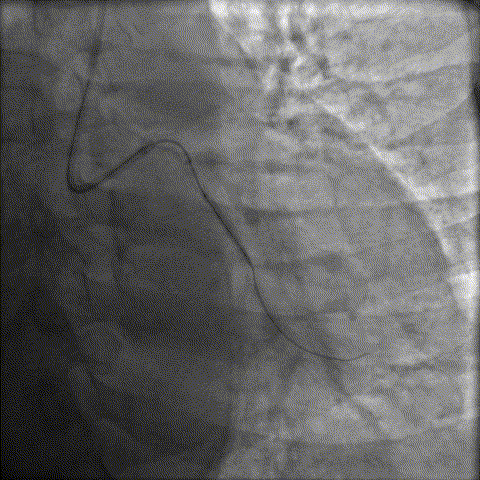

LAD近中段重度钙化伴迂曲,中段重度狭窄;LCX开口重度狭窄,近中段重度钙化,中段原支架完全闭塞

LCX开口重度狭窄